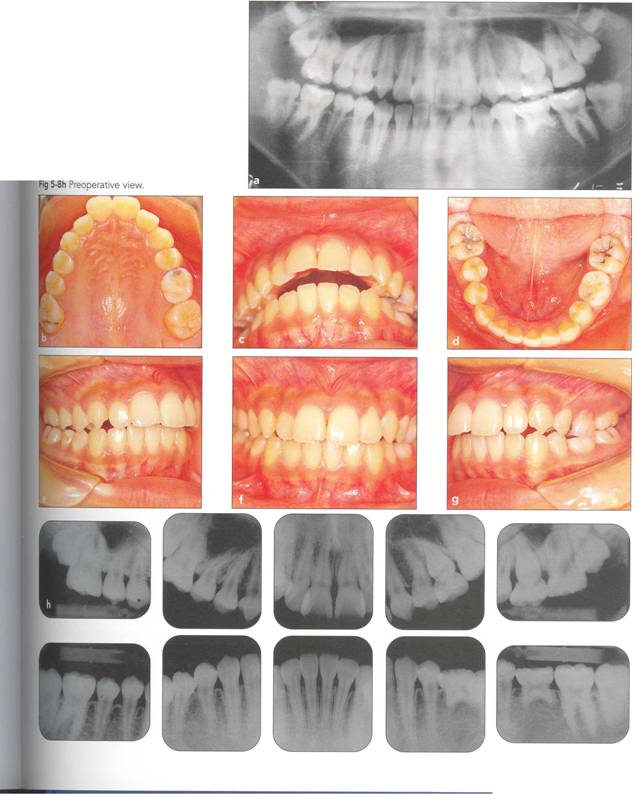

Fi 545e45f g 5-8 Transplantation of an extracted tooth (for orthodontic reasons) to the area of a con genitaJIYrnissingrnandibular premolar. |

Fi 545e45f g S.8a Preoperative panoramic view. The maxillary left first premolar will be extracted for orthodontic reasons and transplanted to the area of mandibular left second premolar in a 15year-old female. Fi 545e45f gs S-8b to 5-89 Preoperative intraoral view. Fi 545e45f g S-8h Preoperative view. |